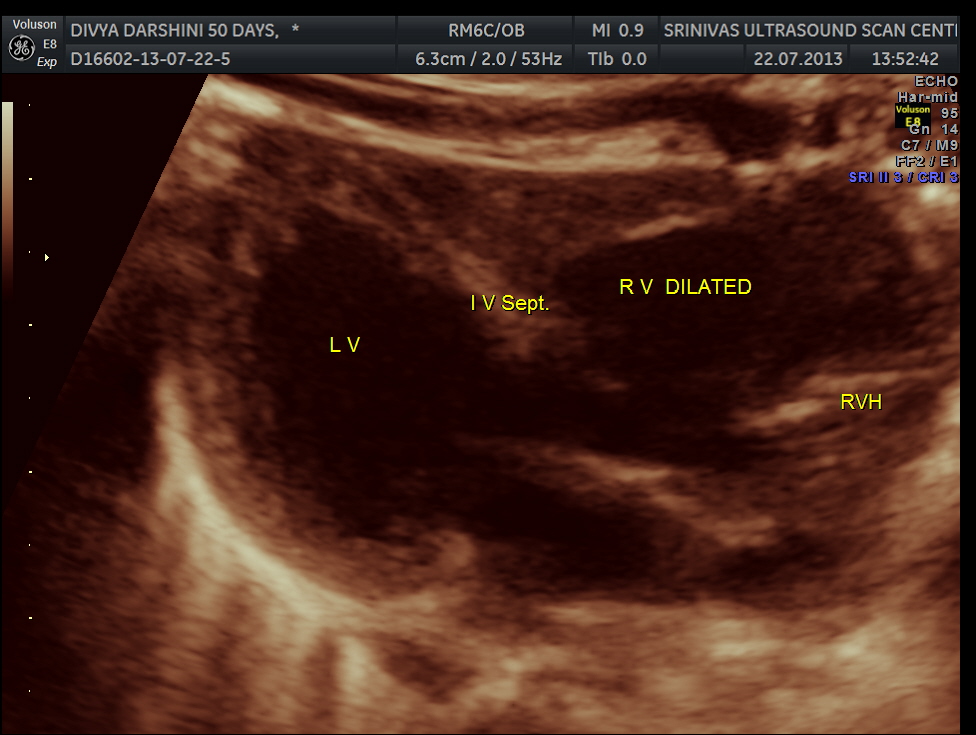

The following pictures are of the heart of the child .

The IVS straddling the aorta is prominently seen ; The RV is mildly dilated . Though the pulmonary artery was difficult to comment on , I would still go with TETRALOGY OF FALLOT with RENAL DYSPLASIA , which makes it complicated.